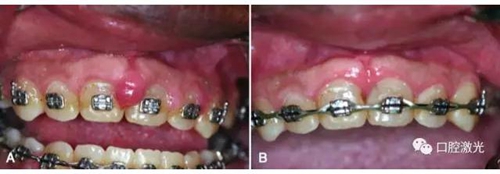

激光牙齦切除術治療牙齦增生

A:手術前,B:手術后10天效果